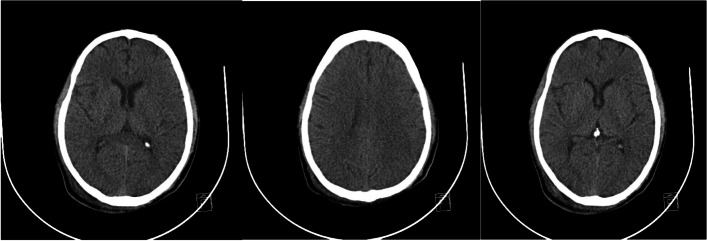

He was intubated and femoral catheterization was performed. Three vials of bicarbonate were intravenously administered. He underwent hemodialysis for eight hours but remained unresponsive. Serum/urine ketone and blood sugar were later returned to be positive and 411 mg/dL, respectively, indicating the possible presence of DKA. After initiation of insulin infusion, serum bicarbonate level started to rise. During admission, he had developed brain edema (Fig. 1). However, after appropriate treatment for DKA, the patient regained consciousness and was extubated. Since there were consolidations in his chest X-ray and lung computed tomography scan (Figs. 2 and 3), antibiotics and sepsis workup were ordered. He was initially treated by meropenem and vancomycin (for aspiration pneumonia); however, after consulting with the attending infectious disease specialist, he was started on levofloxacin. He was also receiving intravenous potassium, pantoprazole, heparin with prophylactic dose, and nebulized N-acetyl cysteine. Due to melena, endo-colonoscopy was performed but was reported to be normal. The other complication our patient experienced was deep venous thrombosis at the site of femoral catheter which mandated anticoagulation therapy with heparin drip. Diabetic ketoacidosis re-occurred twice more during the hospitalization. With the legitimate dose of methadone prescribed by psychiatrics, DKA completely resolved, and he was discharged home completely symptom-free after four weeks. Serial venous blood gas analysis, blood sugar and selected lab tests of the patient during hospital admission are shown in Figs. 4 and 5 and Table 2.

Fig. 2.

Chest X-ray of the patient

Fig. 3.

Lung computed tomography scan of the patient